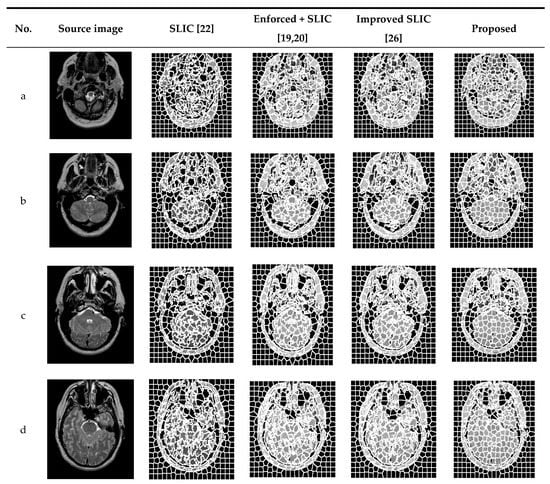

In order to verify the effectiveness of the proposed algorithm, experiments were carried out on several MRI brain images and were compared with traditional SLIC and enforced + SLIC algorithms. Figure 5 shows the segmentation results of traditional SLIC, enforced + SLIC, improved SLIC, and the proposed algorithm in this paper. As shown in Figure 5, after preprocessing, the target areas that are close to the color of the background area are segmented, the gray value consistency of the superpixel blocks is better, and the segmentation results are more accurate.

Figure 5.

The segmentation results of different algorithms.

Compared with SLIC, improved SLIC greatly improved the accuracy of superpixel segmentation and the consistency of superpixel blocks. As can be seen from Figure 5, after adding the local texture features of the image, the image features are better when calculating the similarity between pixels, and the pixels grouped into the same superpixel have more similar features. The superpixel edge of the proposed algorithm coincides with the edge of the target area in the image. The target areas close to the gray value of the background area and the smaller target areas that are misclassified are also significantly reduced. The superpixel blocks are more uniform and regular, and the accuracy of superpixel segmentation and the consistency in the superpixels are further improved in the proposed algorithm.